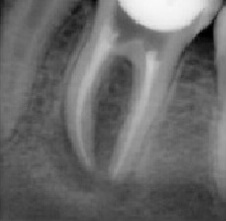

Probleem. Sügav karioosne õõnsus

Lahendus. Kanalid puhastati, valmistati ette täidiseks ja tehti hambaravifoto koos täitematerjaliga.

Sulge hamba juurekanalid. Hammas on valmis edasiseks raviks.